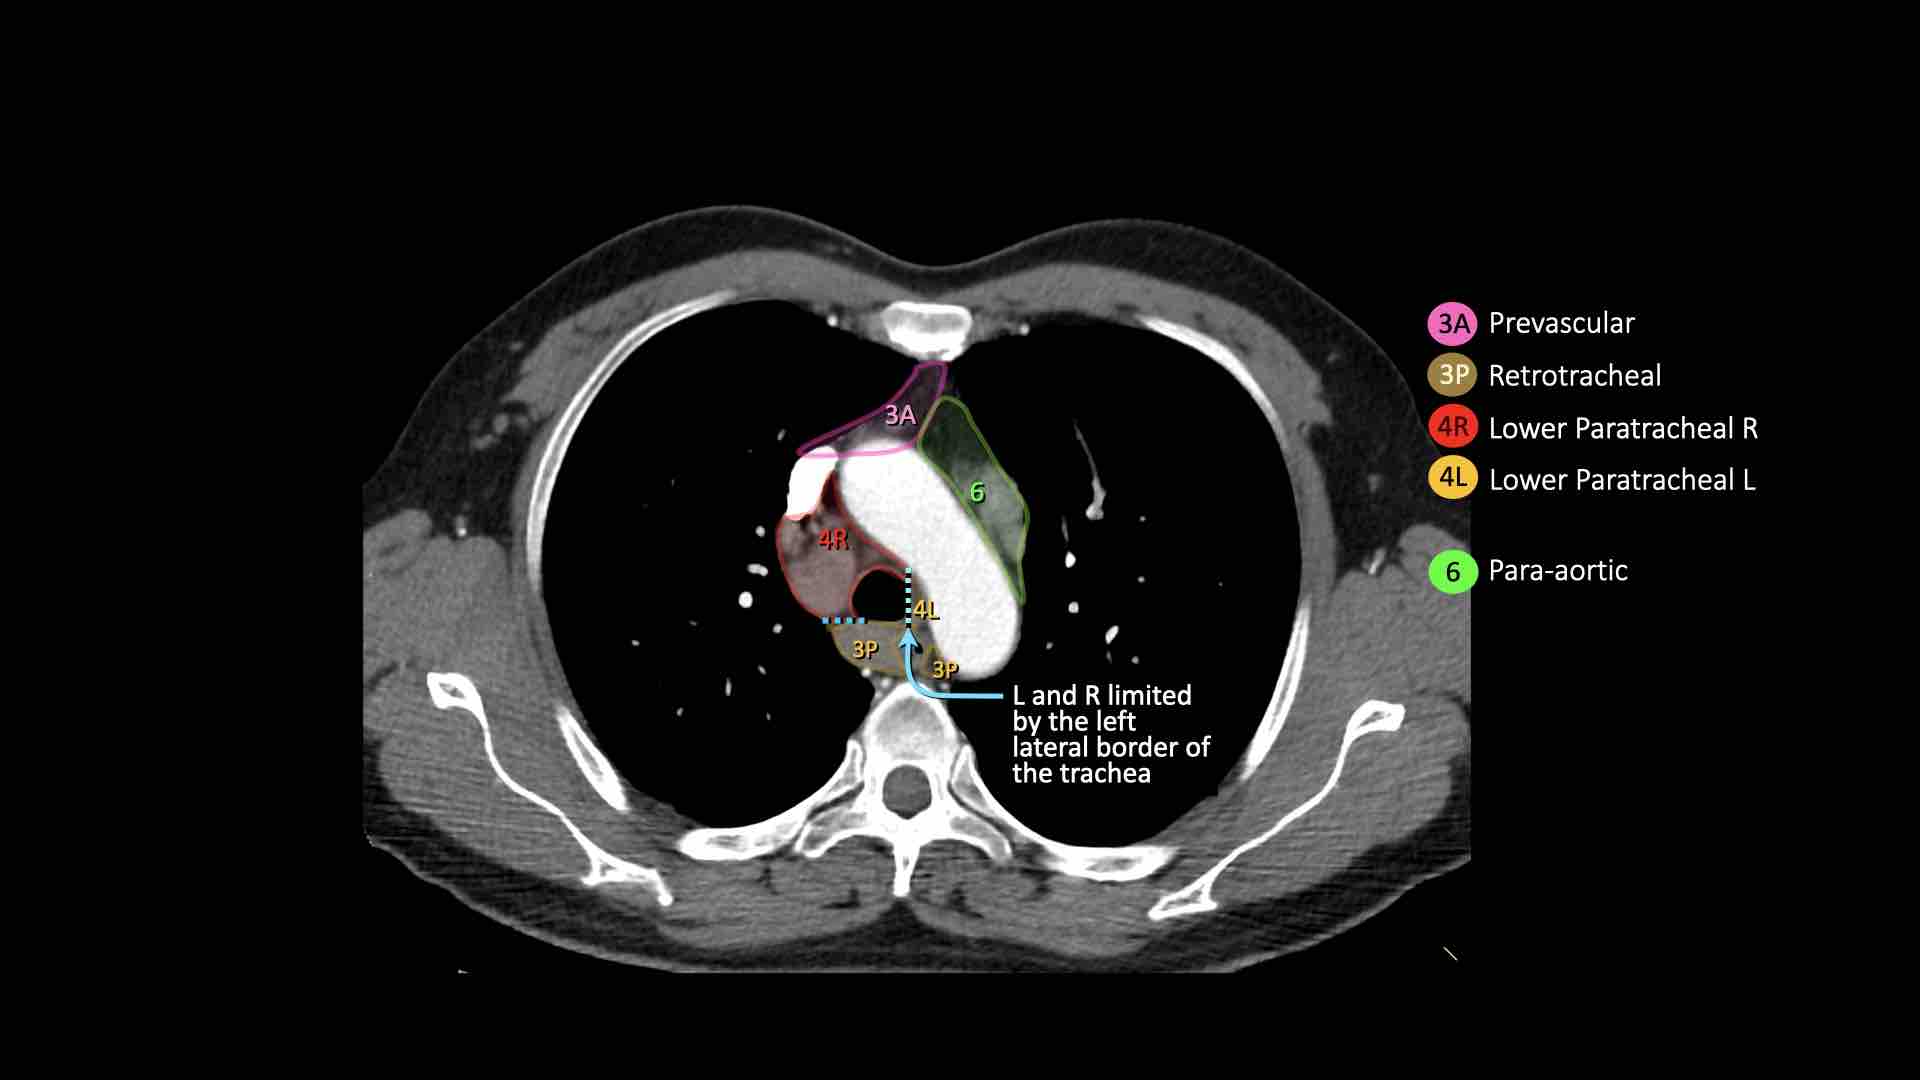

4L. Hạch cạnh khí quản dưới bên trái

Hạch nhóm 4L là các hạch cạnh khí quản dưới nằm bên trái bờ trái của khí quản, giữa đường nằm ngang tiếp tuyến với bờ trên quai động mạch chủ và đường tiếp tuyến với bờ trên động mạch phổi trái.

Nhóm này bao gồm các hạch cạnh khí quản nằm ở phía trong dây chằng động mạch.

Hạch nhóm 5 (cửa sổ phế động mạch) nằm ở phía ngoài dây chằng động mạch.

Bên trái là hình ảnh ngay trên mức thân động mạch phổi, cho thấy các hạch cạnh khí quản dưới bên trái và bên phải.

Ngoài ra còn có các hạch nhóm 3 và nhóm 5.

Bên trái là hình ảnh ở mức phần dưới khí quản, ngay trên carina.

Bên trái khí quản là các hạch 4L.

Lưu ý rằng các hạch 4L này nằm giữa thân động mạch phổi và động mạch chủ, nhưng không nằm trong cửa sổ phế động mạch, vì chúng nằm ở phía trong dây chằng động mạch.

Hạch nằm bên ngoài thân động mạch phổi là hạch nhóm 5.